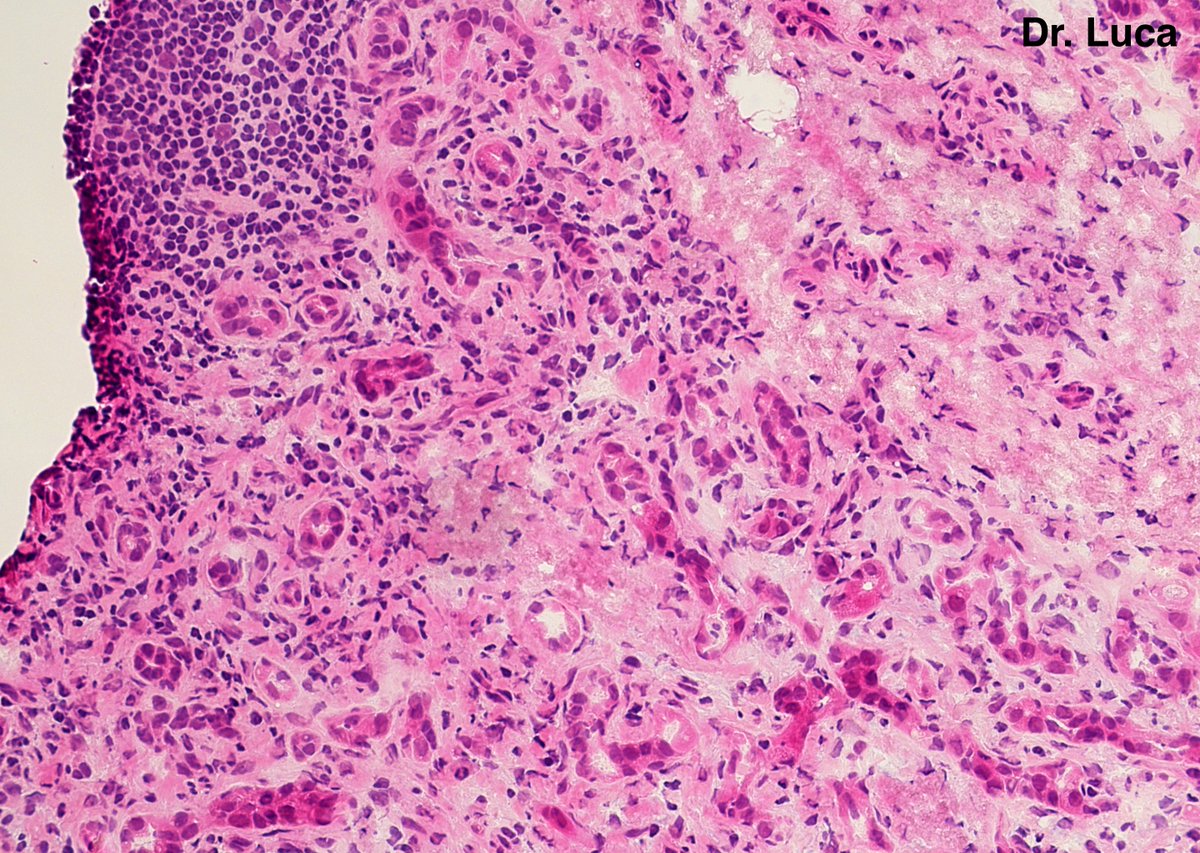

@Pathmath1 @SumantaDas_7 @PoloniaAntonio @ivanaspath @AnapathResident @bansar7 @goziemnweke @Teclis82 @Dr_Brian_Cox @DrBMcGinn @ariella8 @nusrat_xahra @DrRusella_Mirza @glinglerimek @kis_lorand @Venkateshgilly2 @DrBonita16 @DrPayelMondal @DrGeeONE @anjuthevirgo @niki_2389 @pepeheffernan @AngeloCassisa @NeoCrazee @TristanRutland7 Yes, it's a cancer with PNI...I show you the "superficial" layer of this cancer...what is the cancer? and what is the organ? #Pathology #GIpath #PathTwitter #PathResidents #pathboards